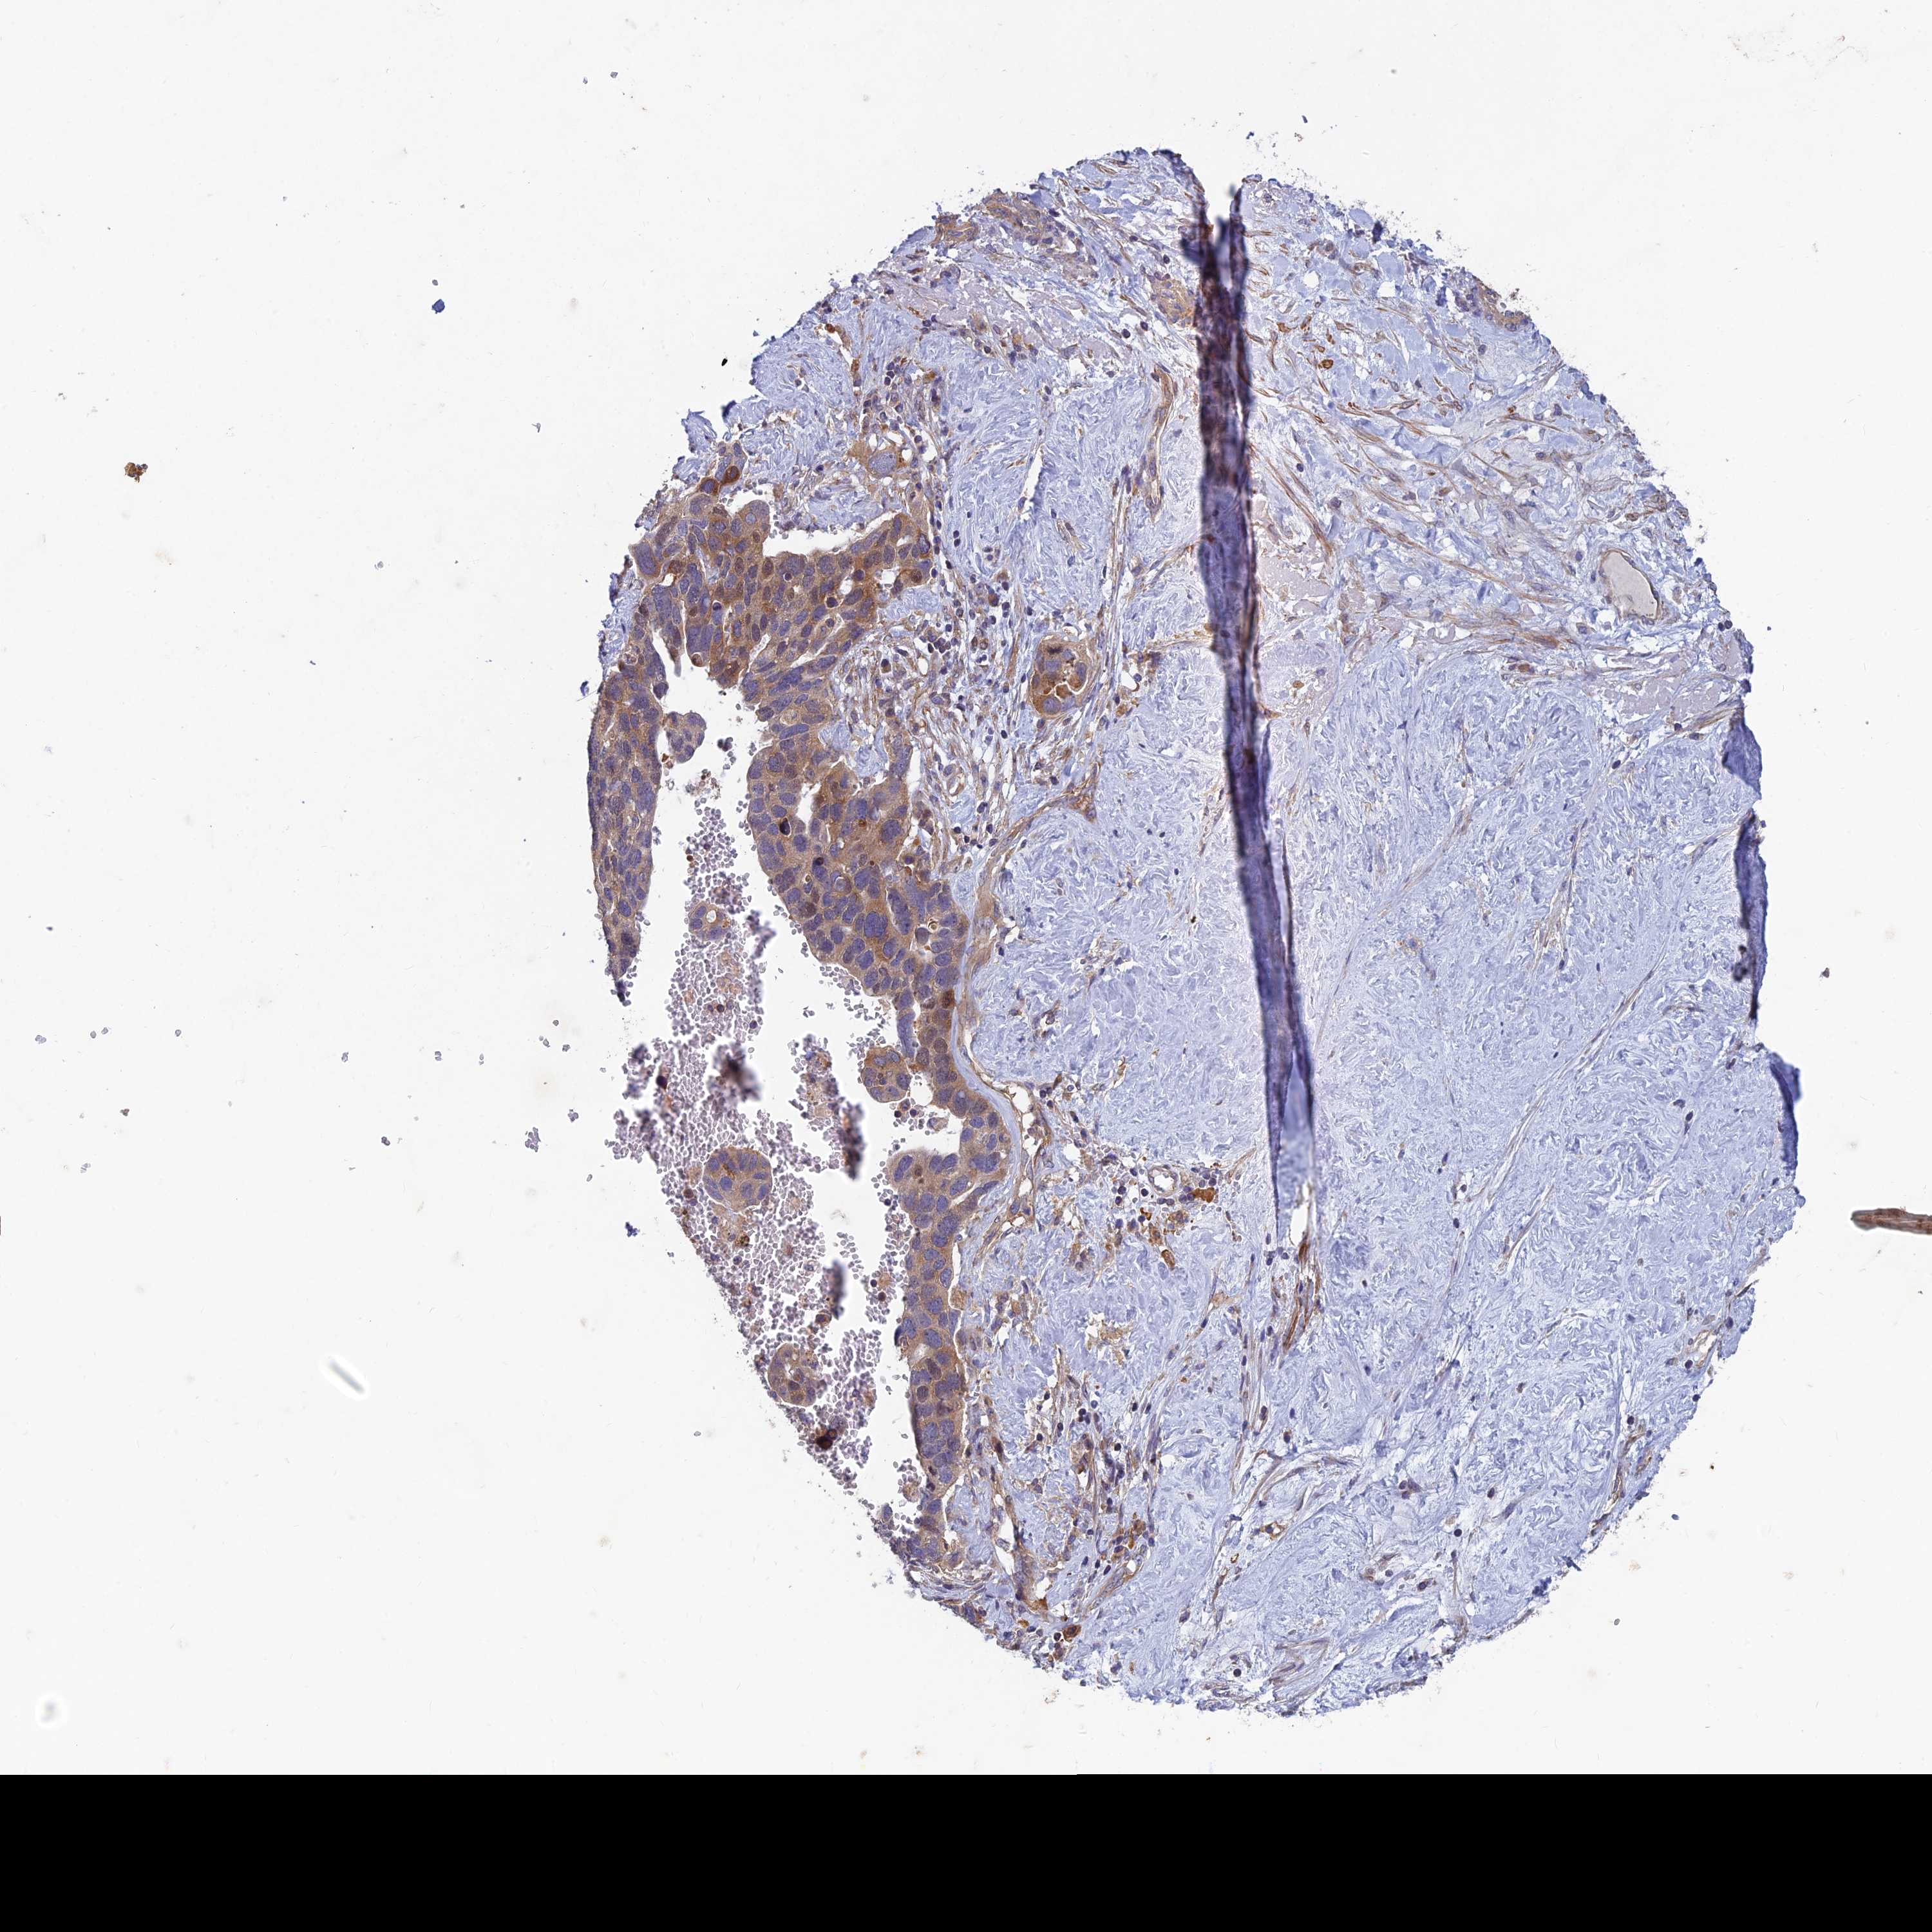

OVARIAN CANCER - Protein expressioni

A mouse-over function shows sample information and annotation data. Click on an image to view it in a full screen mode. Samples can be filtered based on level of antibody staining by selecting one or several of the following categories: high, medium, low and not detected. The assay and annotation is described here.

Note that samples used for immunohistochemistry by the Human Protein Atlas do not correspond to samples in the TCGA dataset.

Antibody stainingi

Antibody staining in the annotated cell types in the current human tissue is reported as not detected, low, medium, or high, based on conventional immunohistochemistry profiling in selected tissues. This score is based on the combination of the staining intensity and fraction of stained cells.

Each image is clickable and will lead to virtual microscopy that enables deeper exploration of all samples and also displays staining intensity scores, fraction scores and subcellular localization as well as patient and tissue information for each sample.

Antibody HPA039613

Staining

High

Medium

Low

Not detected

Intensity

Strong

Moderate

Weak

Negative

Quantity

>75%

75%-25%

<25%

None

Location

Nuclear

Cytoplasmic/membranous

Cytoplasmic/membranous,nuclear

Cystadenocarcinoma, serous, NOS

Carcinoma, endometroid

Cystadenocarcinoma, mucinous, NOS

Carcinoma, NOS